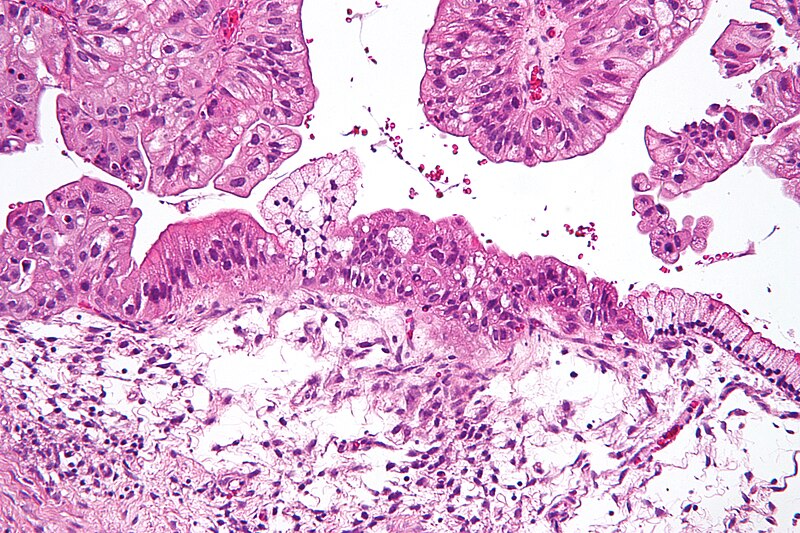

Biopsja

Biopsja jest badaniem medycznym powszechnie wykonywanym przez chirurga, radiologa interwencyjnego lub kardiologa interwencyjnego. Proces ten polega na pobraniu próbki komórek lub tkanek do badania w celu określenia obecności lub zakresu choroby. Tkanka jest następnie utrwalana, odwadniana, osadzana, sekcjonowana, barwiona zanim zostanie ogólnie zbadana pod mikroskopem przez patologa; może być również analizowana chemicznie. Biopsje są najczęściej wykonywane w celu uzyskania wglądu w ewentualne stany nowotworowe lub zapalne. >>>